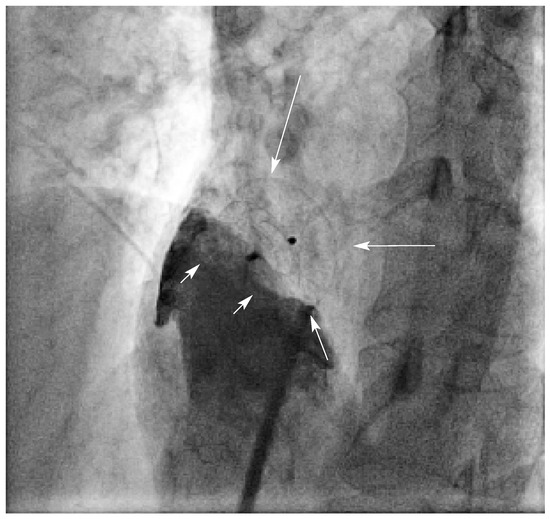

Coronary and Peripheral Thromboembolism from a Giant Left Atrium

by Marcello Di Valentino, Andrea Menafoglio, Ludwig von Segesser, Jeanne-Marie Segatto and Augusto Gallino

Cardiovasc. Med. 2006, 9(1), 28; https://doi.org/10.4414/cvm.2006.01144 - 27 Jan 2006

We report the case of a patient with a history of mitral valve replacement and a giant left atrium with acute transmural anterior myocardial infarction and concomitant acute occlusion of the right superficial femoral artery [...] Full article